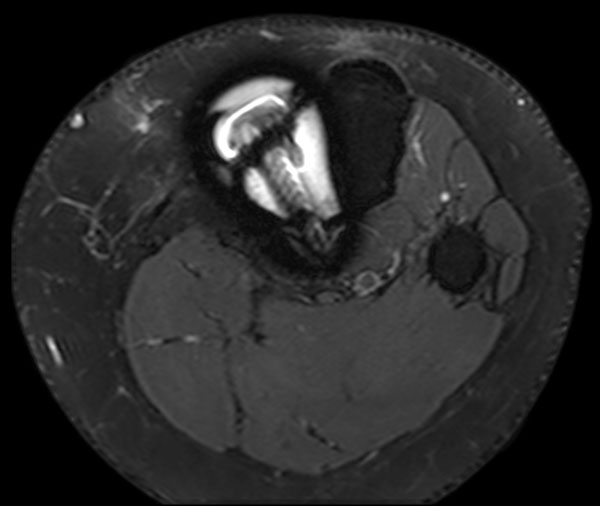

Axial T2w SPAIR

Axial T2w SPAIR (MARS)